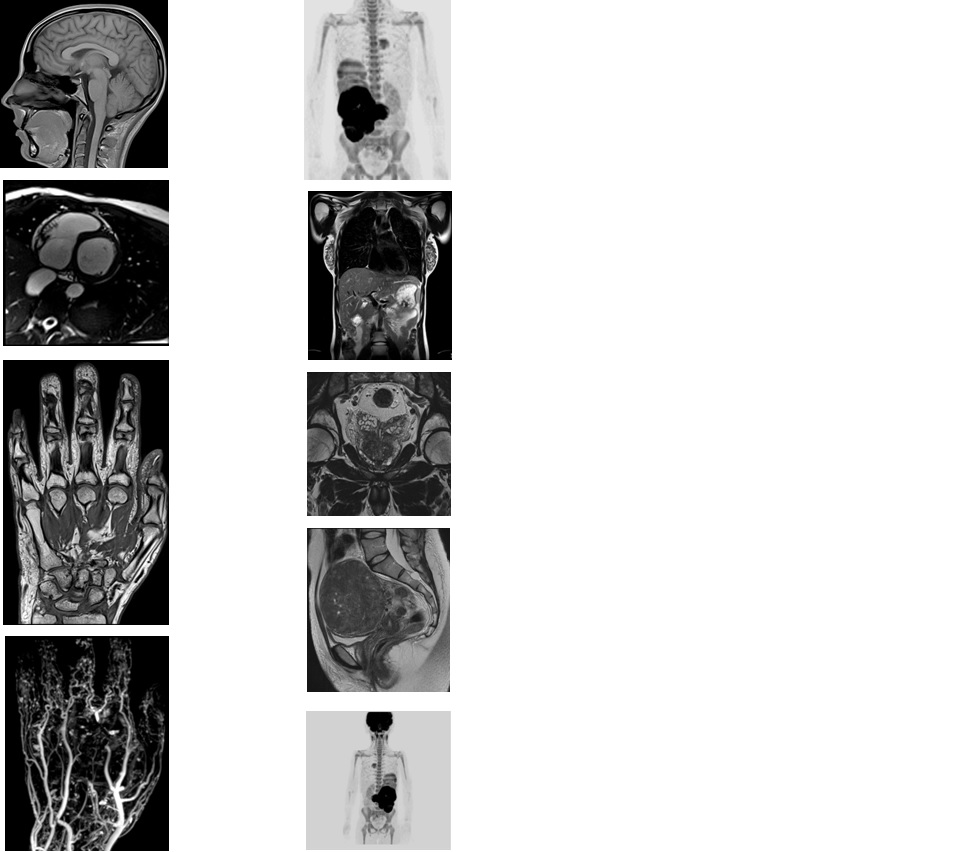

西门子MAGNETOM Aera 纪元四度磁共振可进行神经系统、脊柱、四肢关节、腹部、心脏、血管等全身各个系统的不同疾病的检查,而且能进行波谱分析,对肿瘤的性质鉴定有很高临床价值。对CT无法发现的超早期脑梗塞病变具有无可替代的作用,能发现发病后几分钟内的病灶,为挽救患者生命和改善预后、减少致残率赢得时间。

Tim 4G神经系统临床应用

Tim 4G高密度一体化头颈线圈提供高分辨率头部成像,更多的线圈单元数支持更高的iPAT并行采集因子,有利于减少EPI序列的磁敏感伪影。